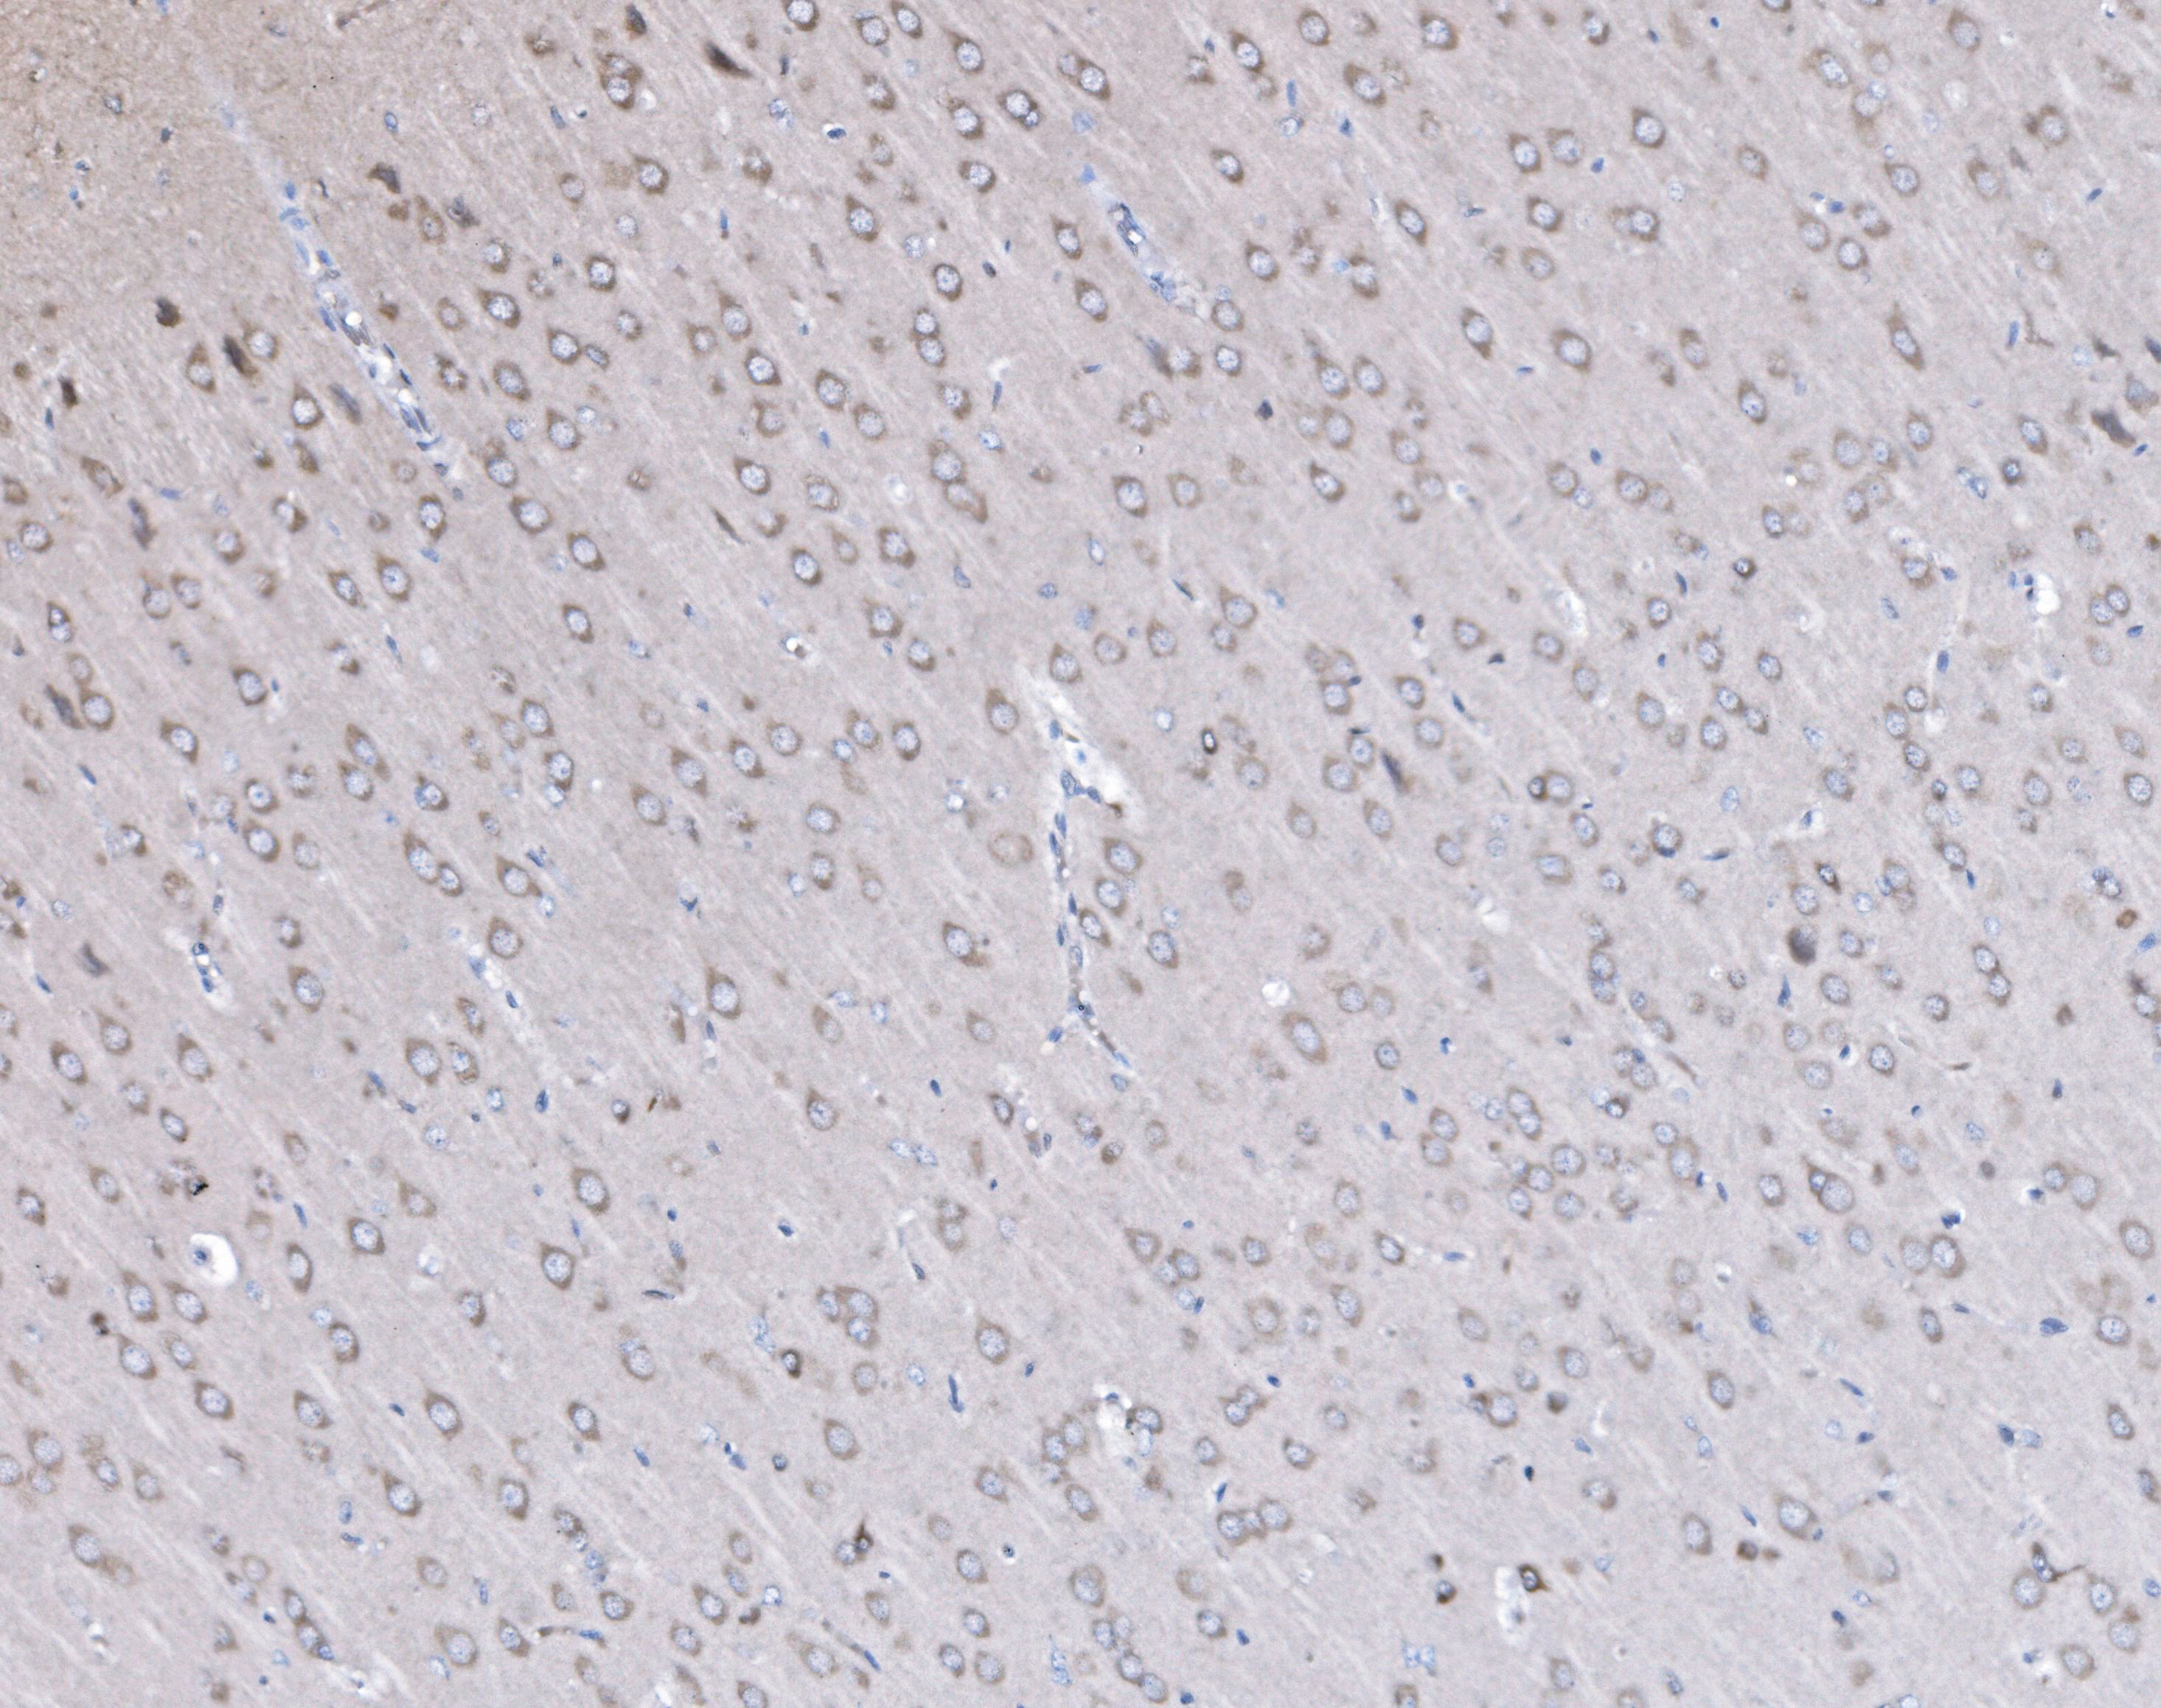

IHC analysis of PSD95/DLG4 using anti-PSD95/DLG4 antibody (BA3304).

PSD95/DLG4 was detected in a paraffin-embedded section of mouse brain tissue. The tissue section was incubated with rabbit anti-PSD95/DLG4 Antibody (BA3304) at a dilution of 1:200 and developed using HRP Conjugated Rabbit IgG Super Vision Assay Kit (Catalog # SV0002) with DAB (Catalog # AR1027) as the chromogen.